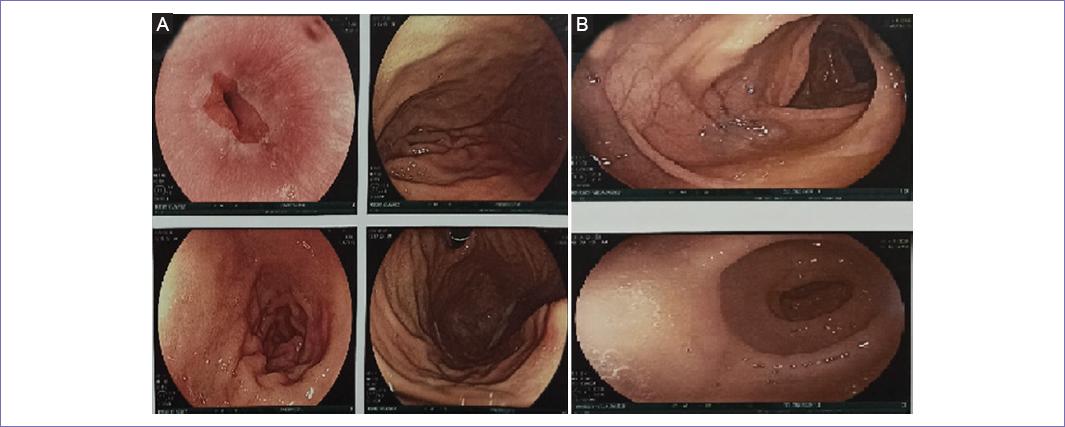

Se continúa con el protocolo diagnóstico mediante panendoscopia y colonoscopia sin reportar alteraciones y/o actividad tumoral (Fig. 3). La mamografía reportó calcificaciones benignas bilaterales y ganglios axilares de morfología inflamatoria; BIRADS (breast imaging reporting and data system) categoría 2 (Fig. 4).

Figura 3 A: panendoscopia que muestra mucosa del esófago y estómago normal. B: colonoscopia que muestra mucosa colorrectal normal.